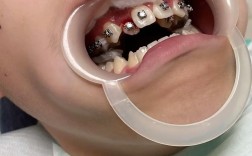

中度增生

- 临床表现:牙龈乳头和牙龈缘明显肿大,呈鲜红色或暗红色,质地松软,易出血,增生组织覆盖牙面1/3-1/2,可能形成“假性牙周袋”,食物嵌塞风险增加,部分患者有胀痛感。

- 图片特征:牙龈乳头呈球形膨出,与邻牙之间形成“V”形或“U”形凹陷,表面光滑或呈分叶状,探诊深度增加(图片中可见牙龈组织明显突出,覆盖部分牙面,牙龈乳头肿大如“小球”,颜色鲜红)。